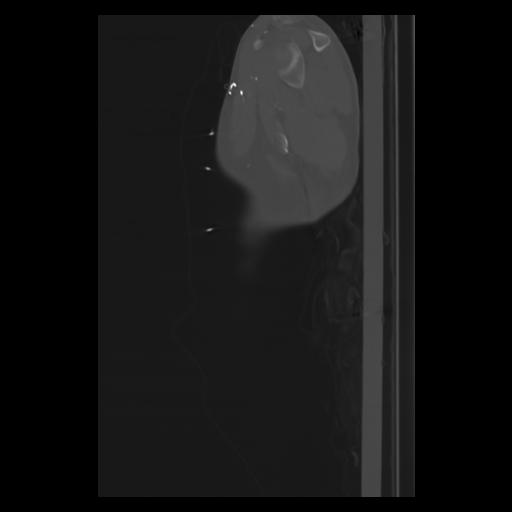

30 CUERPO,CE,Sagittal,3.000,CUERPO,Sagittal,